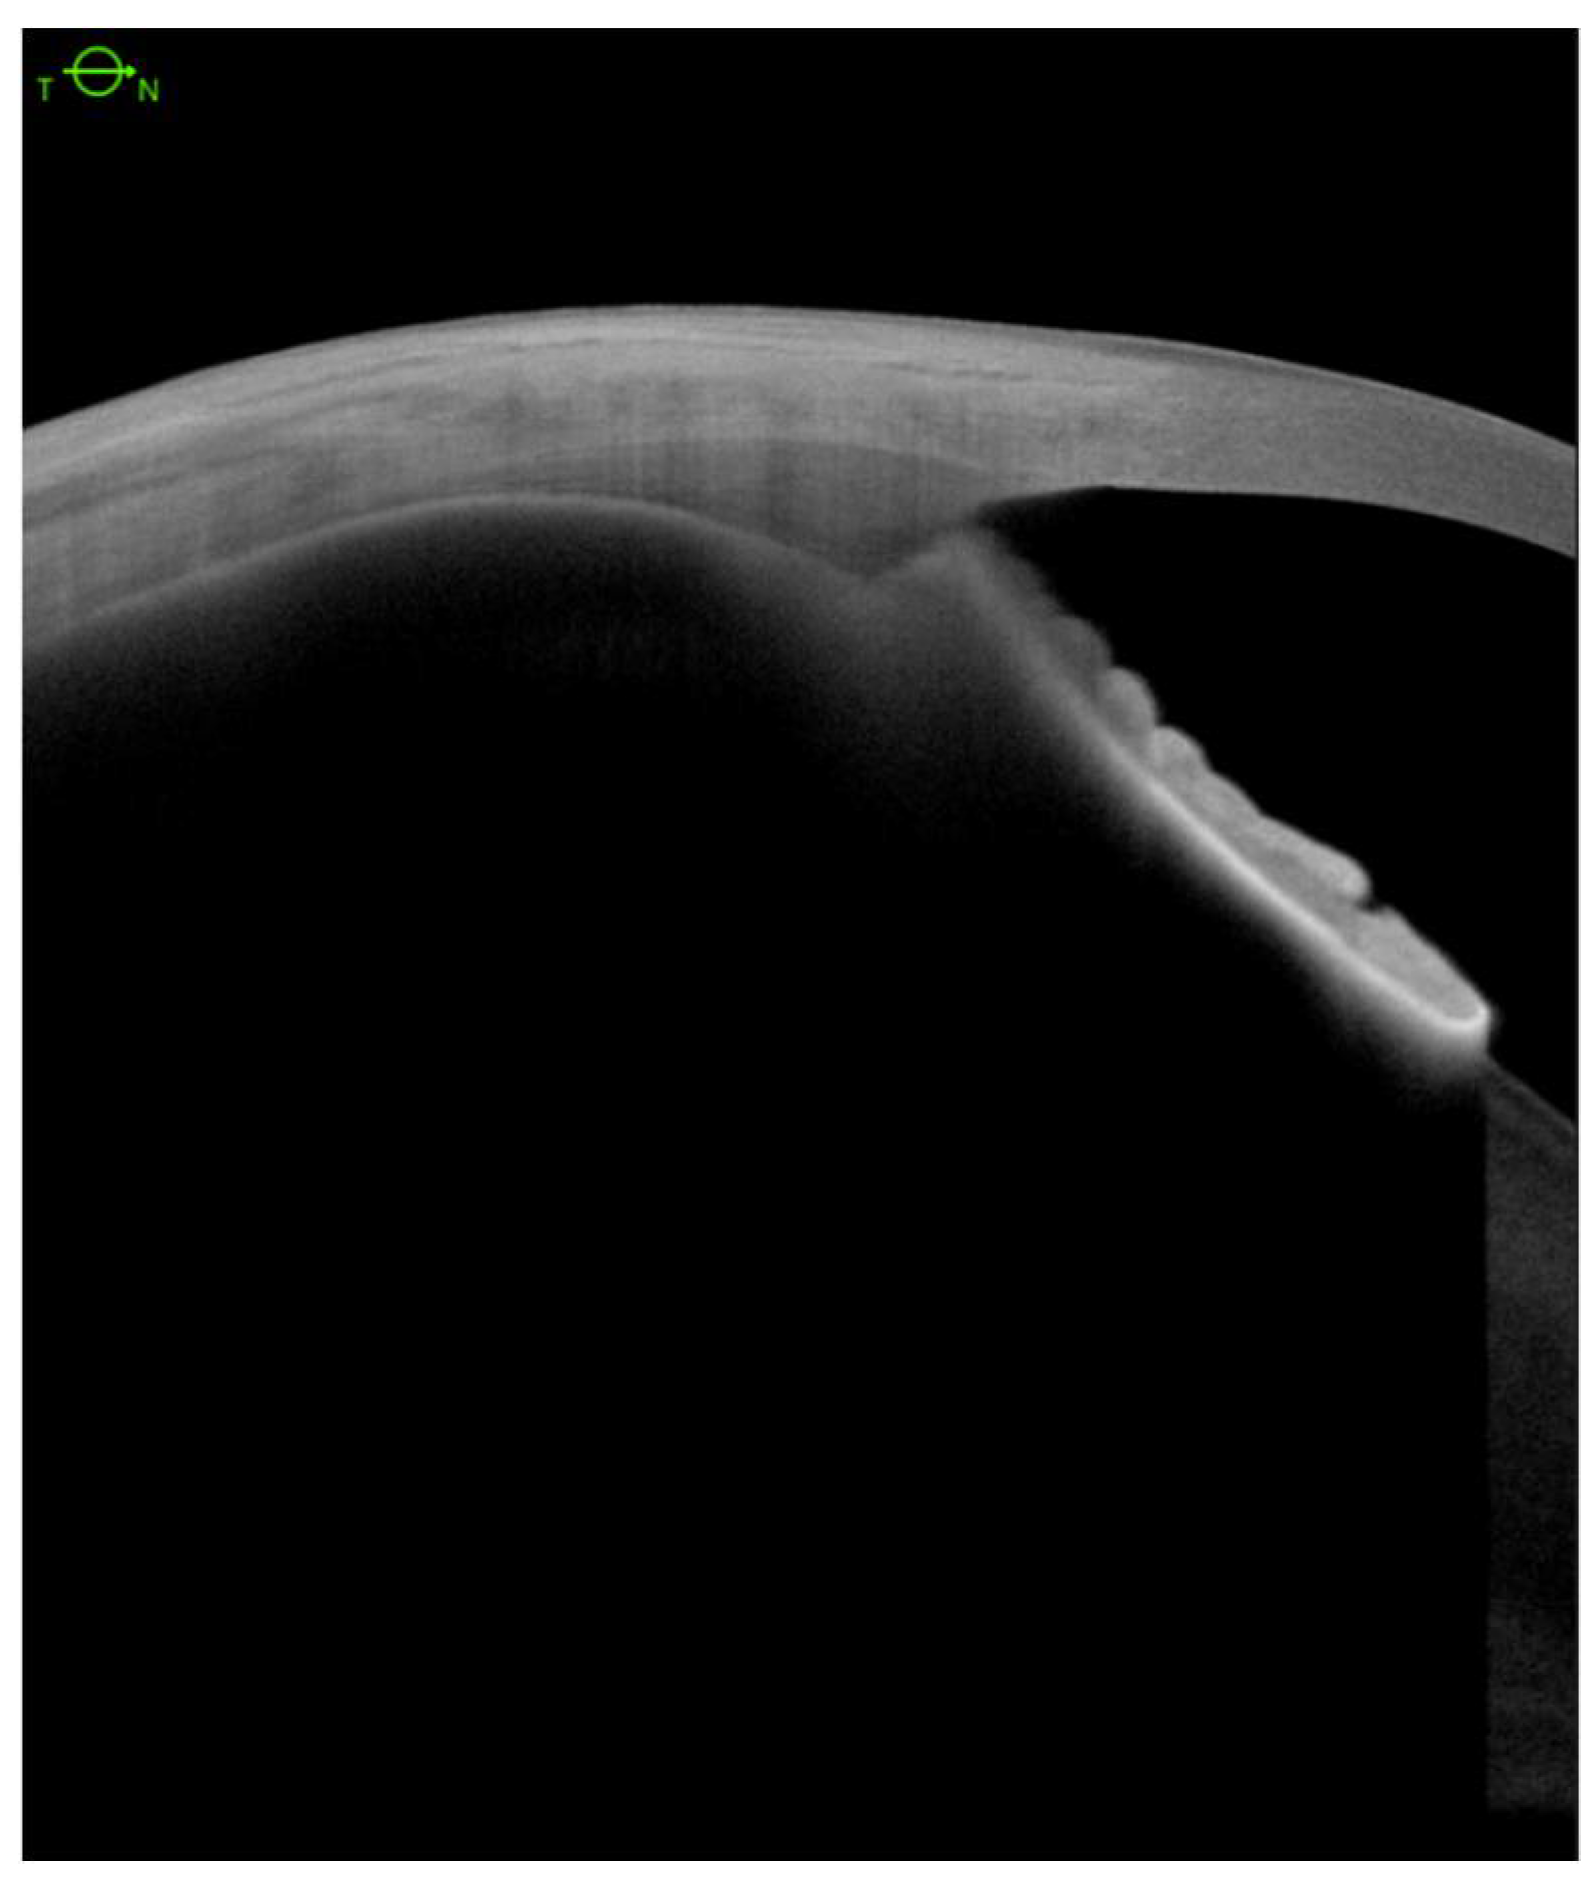

Encircling Scleral Buckling Surgery for Severe Hypotony with Ciliary Body Detachment on Anterior Segment Swept-Source Optical Coherence Tomography: A Case Series

2. Materials and Methods

360° Scleral Buckling Surgery

3. Results